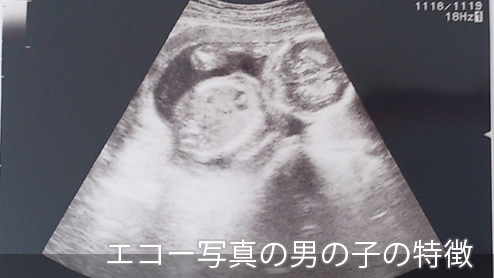

19週で性別判明 男の子と確定したエコー写真 ぽむらいふ おうちと暮らしを楽しむ

2人目が初男の子 写ったシンボルにびっくり エコー写真で振り返る妊婦生活 たまひよ